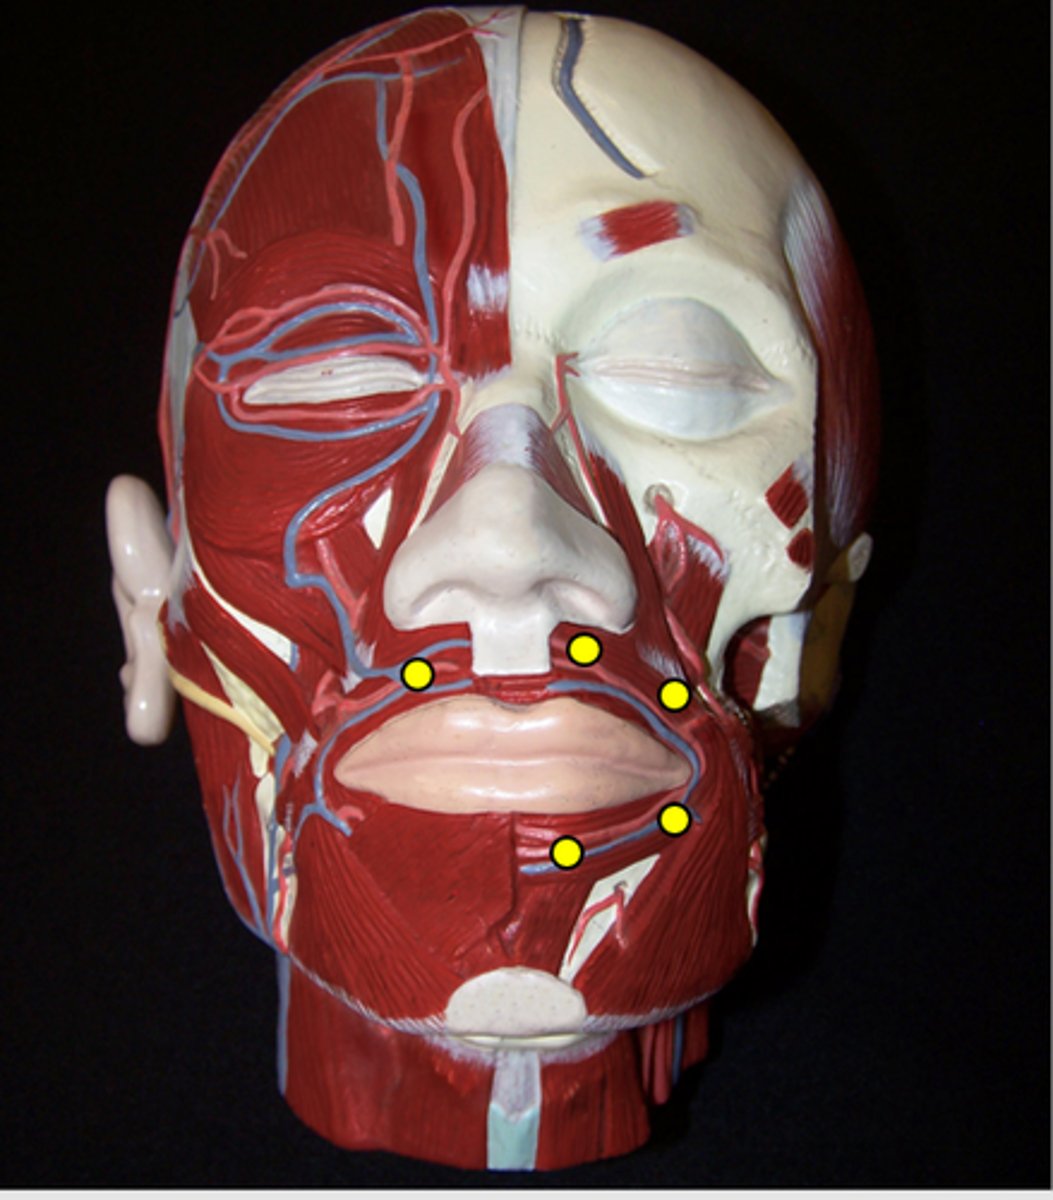

Orbicularis Oris

Levator Labii Superioris

Depressor Anguli Oris

Depressor Labii Inferioris

Mentalis

Buccinator